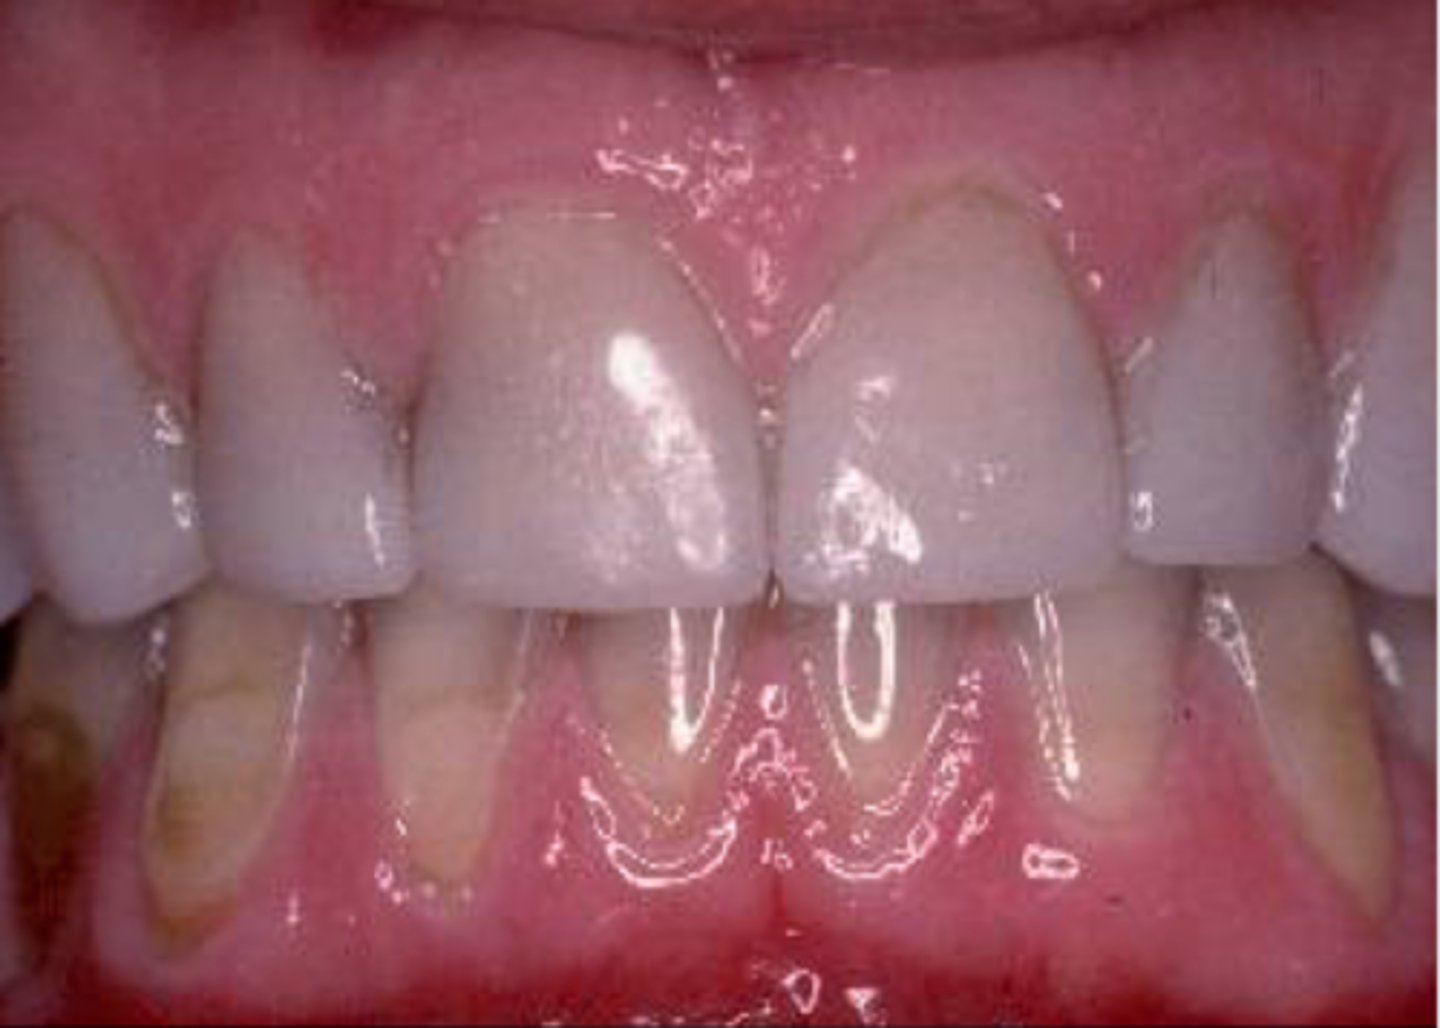

Patient does not like look on canine (pictured), asked what it was

Hypoplasia